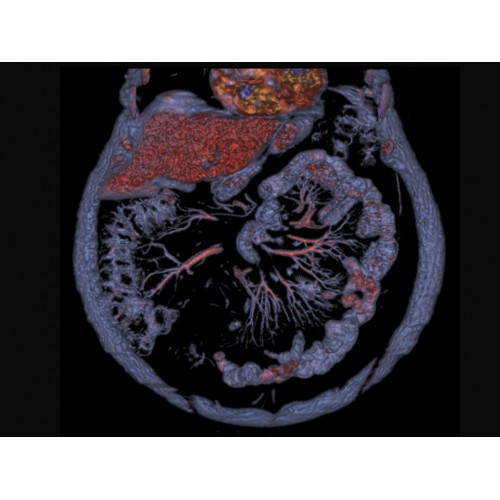

Основные области применения

КТ аппарат GE Optima CT520 используется для диагностики широкого спектра заболеваний:

Онкология

• Раннее выявление новообразований и контроль эффективности лечения.

• Планирование лучевой терапии с высокой точностью.